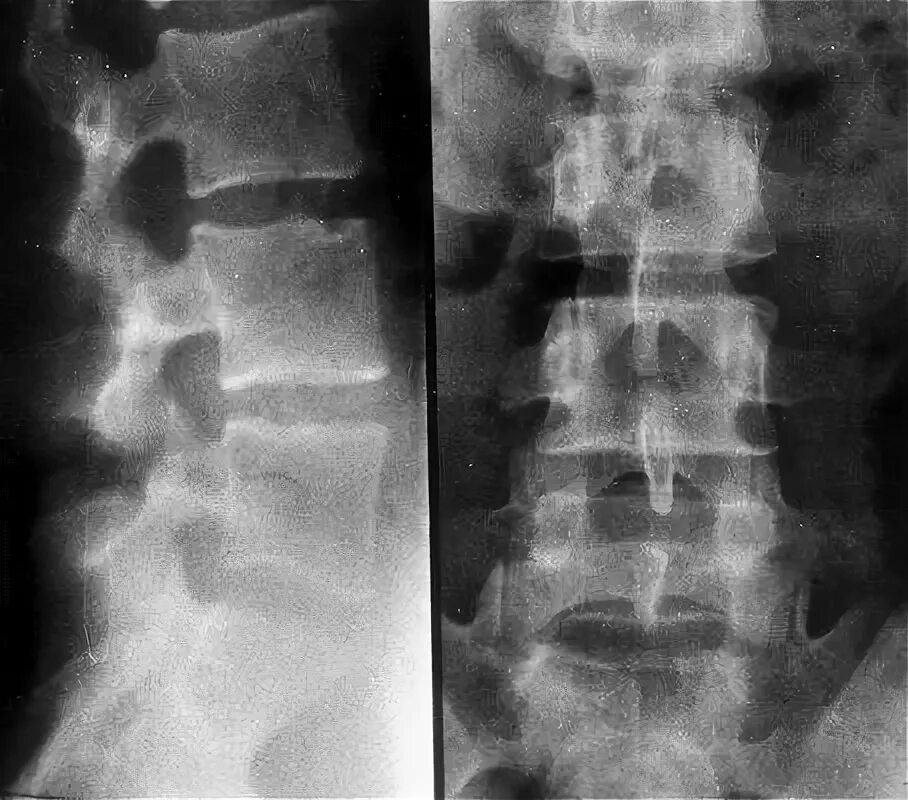

Перелом отростка поясничного позвонка